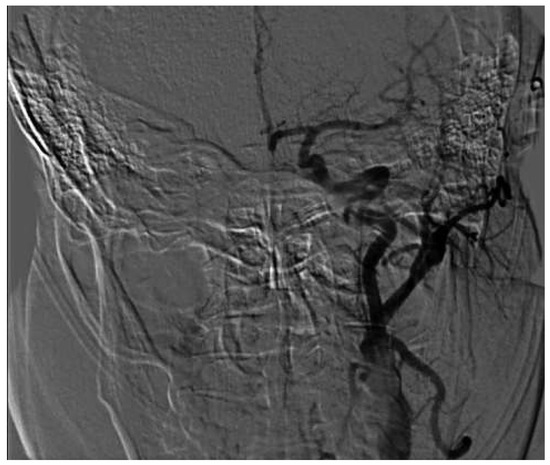

Mechanical Thrombectomy After Embolic Internal Carotid Artery Occlusion in Acute Stroke

by Christophe A. Wyss, Anahita Dastoor and Roberto Corti

Cardiovasc. Med. 2014, 17(2), 51; https://doi.org/10.4414/cvm.2014.00204 - 19 Feb 2014

A 34-year old woman presented to the emergency department with a wake-up stroke, after onset of a sensomotoric paresis of the right arm and motoric aphasia [...] Full article

Figure 1